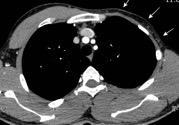

Masa axilar izquierda y derrame pleural derecho. Implantes pleurales, paraespinales . Ganglios en mamaria interna. Linfoma B difuso

Jaffe ES. Diagnosis and Classification of Lymphoma: Impact of Technical Advances.

2005. Masa pulmonar.